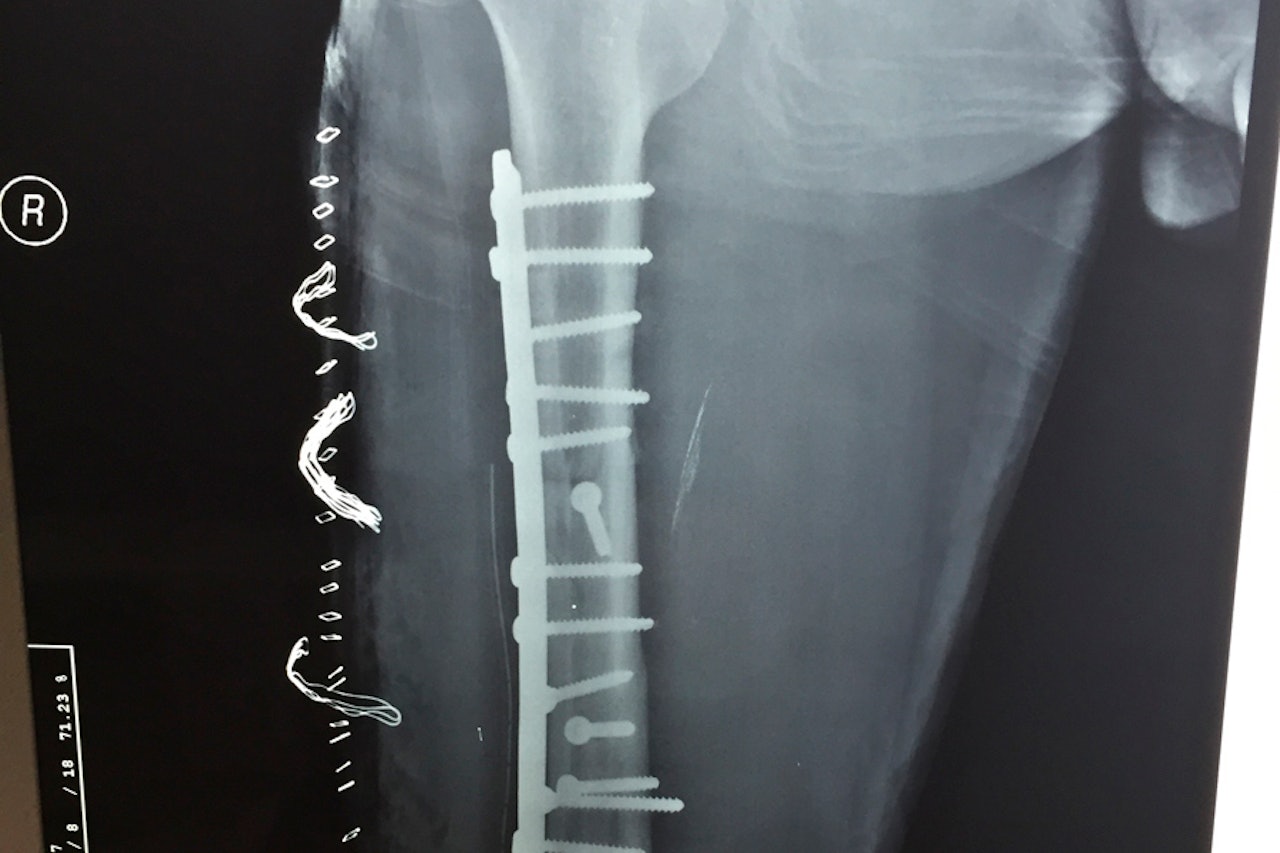

Han vant nemlig en valgfri bok fra Fri Flyt eller t-skjorte levert av ffshop.no. Med god margin fikk han flest stemmer med sitt brukne lårbein. Beinet ble skadet i en wakeboardulykke, og han fikk dermed satt en rask stopper for den kommende vintersesongen.